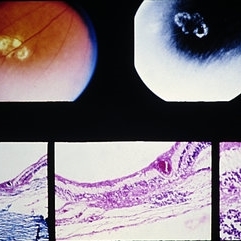

Slide 9-94

Slide 9-94

Feb 26 2019 by Lancaster Course in Ophthalmology

Macular disciform lesion in the ocular histoplasmosis syndrome. Note choroidal scar with vessels (arrow) extending through a break in Bruch's membrane.

Condition/keywords: Bruch's membrane, disciform macular lesion, ocular histoplasmosis syndrome (OHS)

Slide 9-66

Slide 9-66

Feb 26 2019 by Lancaster Course in Ophthalmology

Midperipheral punched-out lesions in the presumed ocular histoplasmosis syndrome. There is scarring in the choroid and retina, discontinuity in Bruch's membrane, and loss of the RPE. An infiltrate of lymphocytes is present in the subjacent choroid (lower middle and right).

Condition/keywords: Bruch's membrane, ocular histoplasmosis syndrome (OHS), retinal pigment epithelium, scar

Slide 3-15

Feb 20 2019 by Lancaster Course in Ophthalmology

Higher-power view of choroid in presumed histoplasmosis retinochoroiditis, showing marked epithelioid cell infiltrate ( x65).

Condition/keywords: choroid

Slide 3-14

Feb 20 2019 by Lancaster Course in Ophthalmology

Adjacent area to that in Slide 3-13, showing degenerative change and inflammatory infiltrate in presumed histoplasmosis retinochoroiditis ( x25).

Condition/keywords: histoplasmosis, inflammatory infiltrate

Slide 3-13

Feb 20 2019 by Lancaster Course in Ophthalmology

Cystoid macular change with granulomatous inflammation of choroid and retina in eye of patient with presumed histoplasmosis retinochoroiditis ( x25).

Condition/keywords: choroid, cystoid macular degeneration, granulomatous inflammation, histoplasmosis